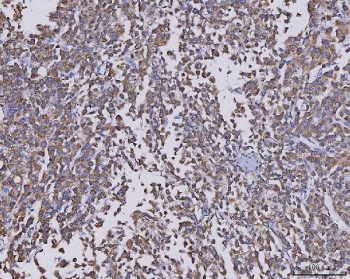

IHC staining of FFPE human liver cancer tissue with CCL14 antibody. HIER: boil tissue sections in pH8 EDTA for 20 min and allow to cool before testing.

IHC staining of FFPE human breast cancer tissue with CCL14 antibody. HIER: boil tissue sections in pH8 EDTA for 20 min and allow to cool before testing.